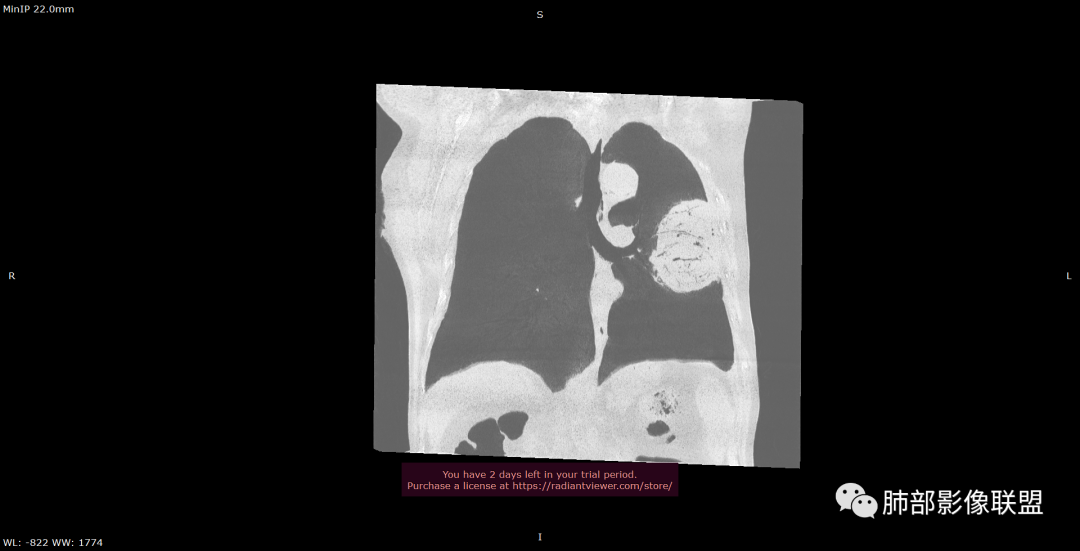

左肺上叶胸膜下肿块,宽基底与胸膜相连,跨叶裂,边缘清晰膨隆,其内支气管充气,部分扩张、僵直,无明显强化,血管造影征,考虑淋巴瘤,鉴别腺癌

左肺胸膜下巨大占位,跨叶裂,宽基底与胸膜相连,胸膜钙化,平扫密度较低,强化不明显,可见内部血管显影,支气管充气征和扩张,考虑为恶性,倾向于淋巴瘤

左侧胸腔巨大肿块,跨叶生长,临近胸膜钙化,边缘模糊,可见支气管影,定位肺内,增强后轻度强化,边缘见血管影,考虑淋巴瘤,鉴别肉瘤

左肺紧贴胸膜巨大肿块,跨叶裂生长,密度均匀,边缘清晰,内支气管略扩张,增强见血管影,强化不明显,胸膜栽赃,钙化,考虑淋巴瘤。

大肿块,边缘光滑,深分叶

肺动脉推移为主,边缘部分进入

大肿块、表面光滑但深分叶,肺门侧支气管堵塞

回头看,内部支气管近端其实不连续,伴随肺动脉不存在

1)部位:周围型或中央型软组织肿块,以周围型为多见,且肿瘤多位于肺上叶。如本例:该肿瘤位于左肺上叶。

2)大小及形态:由于本病恶性程度高,早期症状不明显,发现时肿块均较大。如本例病变巨大。

5)肿瘤强化方式:肺部恶性肿瘤强化程度与其血供丰富程度相关,血供丰富多强化明显,反之则较差。由于PSC 周边实性部分富血供及内部黏液变性、坏死,增强后肿块多数呈轻-中度边缘环形强化或不均匀小斑片状强化。国外学者对照病理发现肿瘤细胞或胶原组织增强扫描时强化,无强化的低密度区代表了黏液样变性区和出血坏死区。